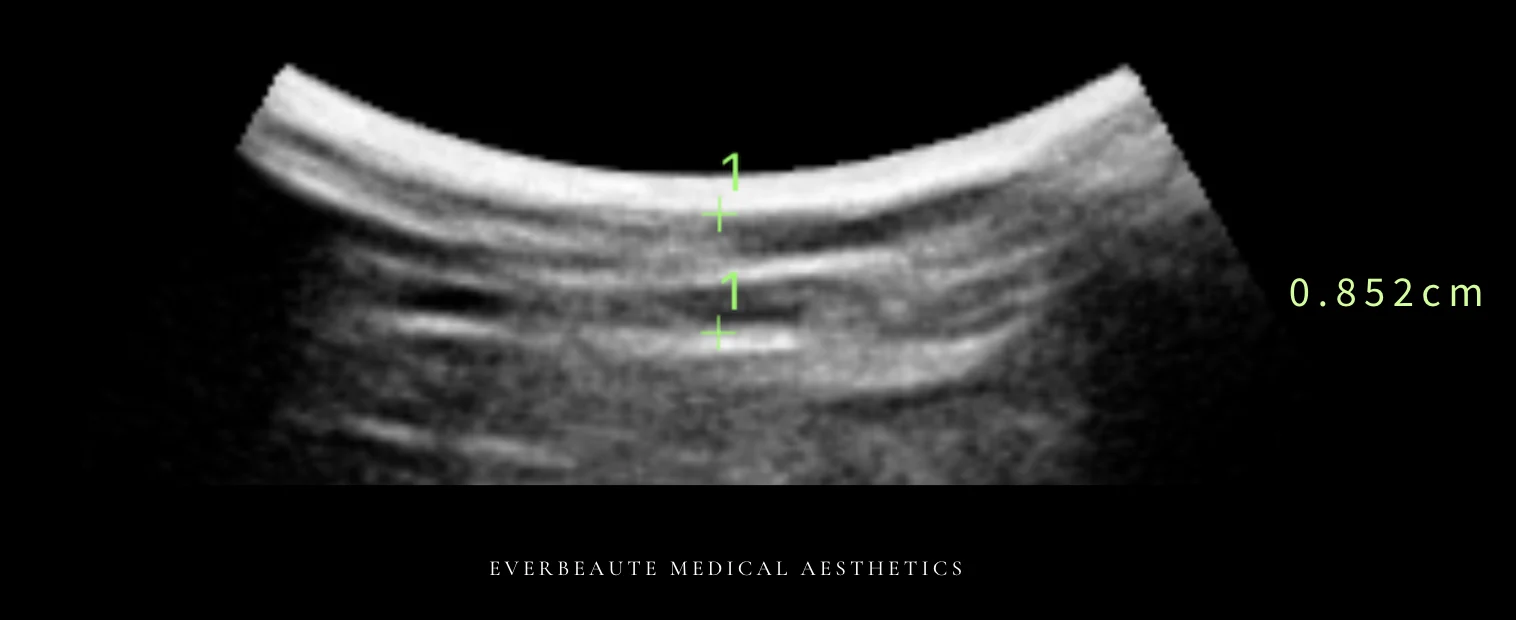

經術前與術後超音波檢查比較,上臂脂肪厚度由1.162公分減少至0.852公分,顯示脂肪厚度下降約26.7%,呈現顯著改善。